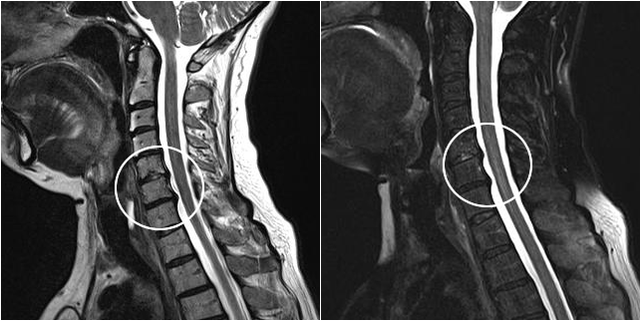

Modern diagnostic methods include MRI and CT, which allow the most accurate examination of the process of destruction of cartilage and bone tissue.Also, with this technique, it is convenient to diagnose hernias and other soft tissue defects near the source of the disease.